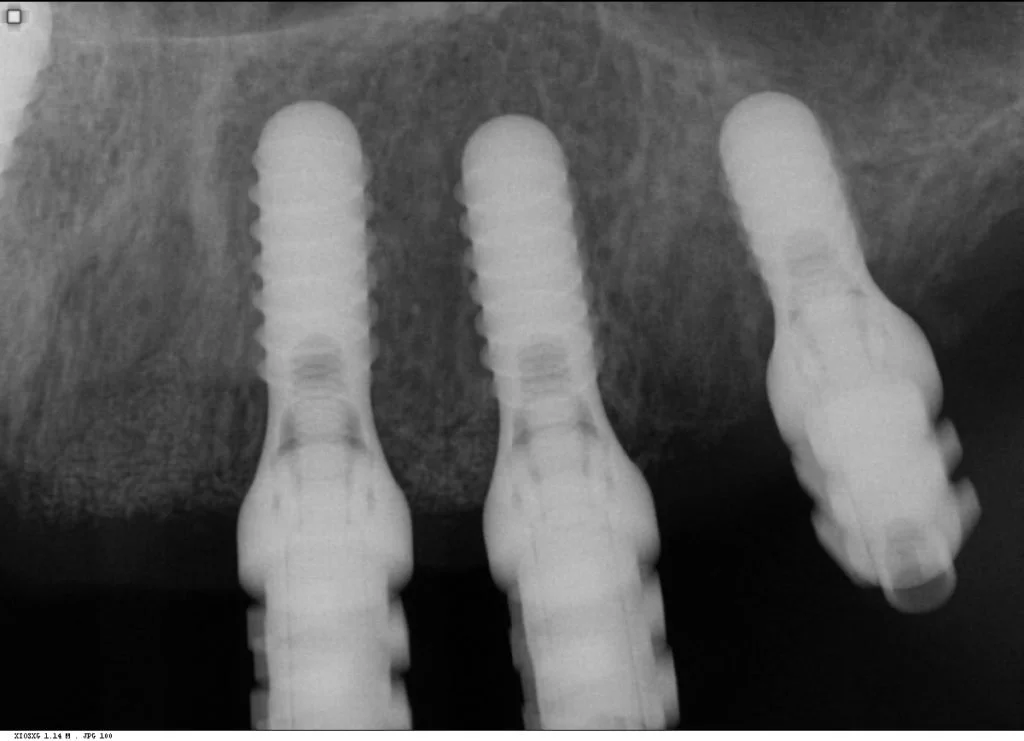

Multiple intra-operative radiographs were taken using depth gauges of gradually increasing diameter to ensure ideal positioning, particularly near vital structures such as the maxillary sinus. Following three months healing, definitive impressions were taken. Radiographs were taken to confirm complete seating of the impression copings prior to splinting of the impression copings and then impression taking.

Records stage: due to the fact that all records were gained by the adjustment and confirmation of the provisional removable complete maxillary denture, records were quite straightforward. The complete denture was copied, flanges were removed, and the resulting guide was then seated over the existing tissue level healing abutments. A PMMA bridge with plastic inserts was constructed digitally in the laboratory and sent for final confirmation prior to construction of the definitive porcelain-fused-to-zirconia bridge. The definitive bridge was inserted and radiographs were taken to confirm full seating and correct emergence profile. Once passivity of fit was confirmed, abutments crews were torque to 35 Ncm, and the access cavities were restored with PTFe tape and composite resin. The occlusion was adjusted to ensure guiding services were smooth, concave and gradually increasing pre-truce in steepness, and smooth shared group function in lateral excursion.

Photo and X-ray at 2 year review